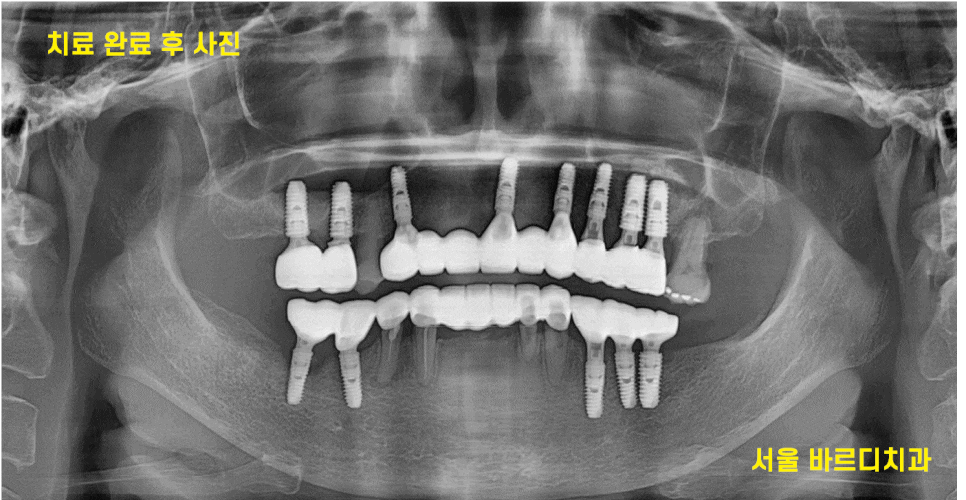

13개의 임플란트 식립 후

전체적인 치아 치료 완료된 사진입니다.

맨 처음 상태가 기억나지 않을 정도이시죠~?